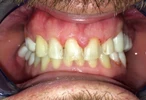

Diş Çapraşıklığı

Diş Çene ve Yüz Bölgesi Gelişim Yetersizlikleri